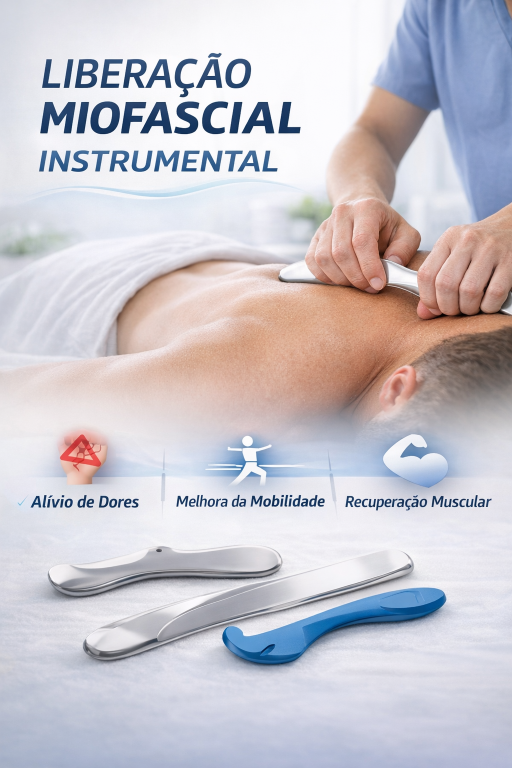

A liberação miofascial instrumental é uma técnica terapêutica utilizada na fisioterapia que consiste na aplicação de instrumentos específicos sobre a pele com o objetivo de mobilizar o tecido miofasci...